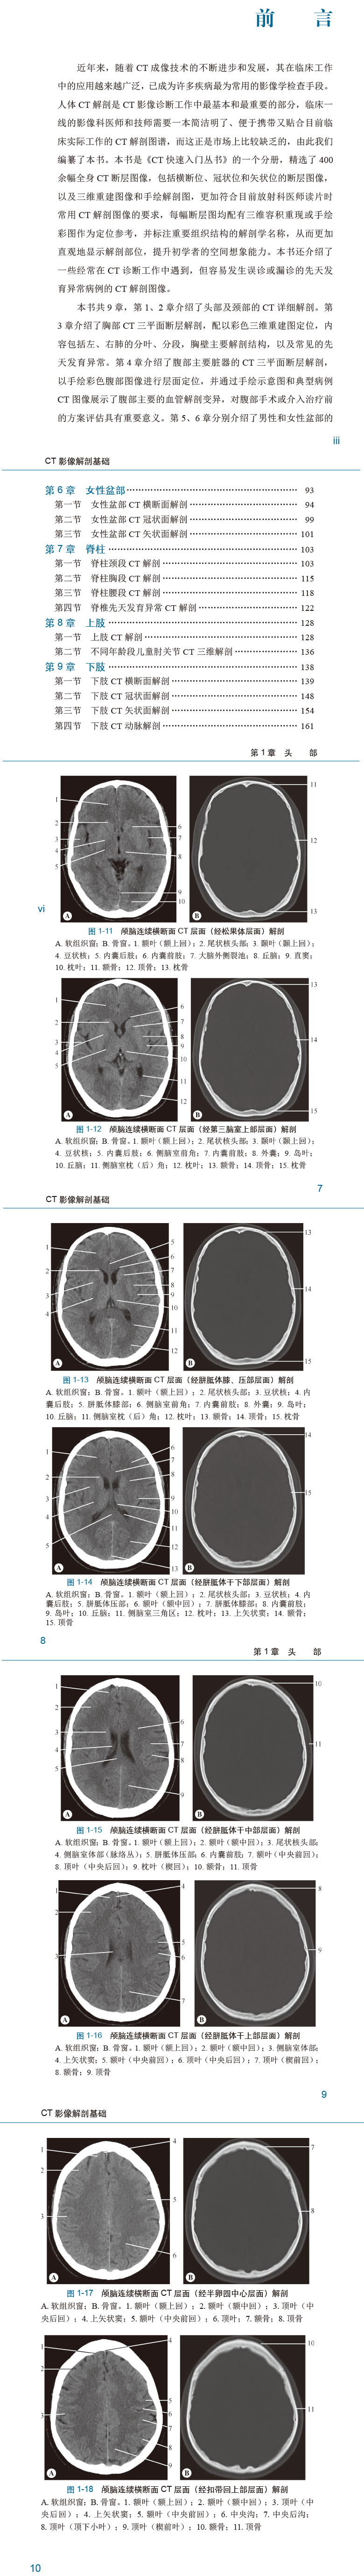

CT影像解剖基础 CT快速入门丛书